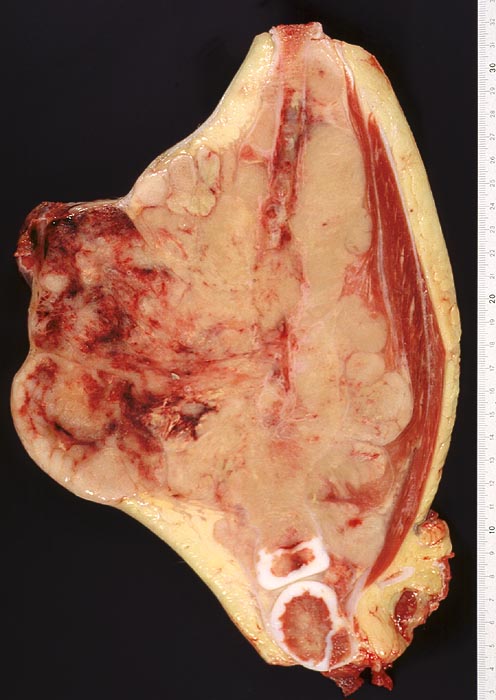

Peripherer primitiver neuroektodermaler Tumor (PNET)

Der Unterschenkel ist auf einen sagittalen Dm von 19cm und einen frontalen Dm von 9cm aufgetrieben. Nach ventral ist an einer Stelle ein Höcker von ca. 10cm Dm entstanden, über dem die Haut hochgradig verdünnt ist. Daneben ein weiterer Höcker, in welchem Tumorgewebe durch die Haut durchgebrochen ist.

Da im Material der Primärbiopsie der Tumor eine positive Reaktion für die neuronspezifische Enolase zeigte, muss er als primitiver peripherer neuroektodermaler Tumor und nicht als Ewingsarkom bezeichnet werden. Beide Tumoren unterscheiden sich im wesentlichen durch die Expression der neuronspezifischen Enolase.